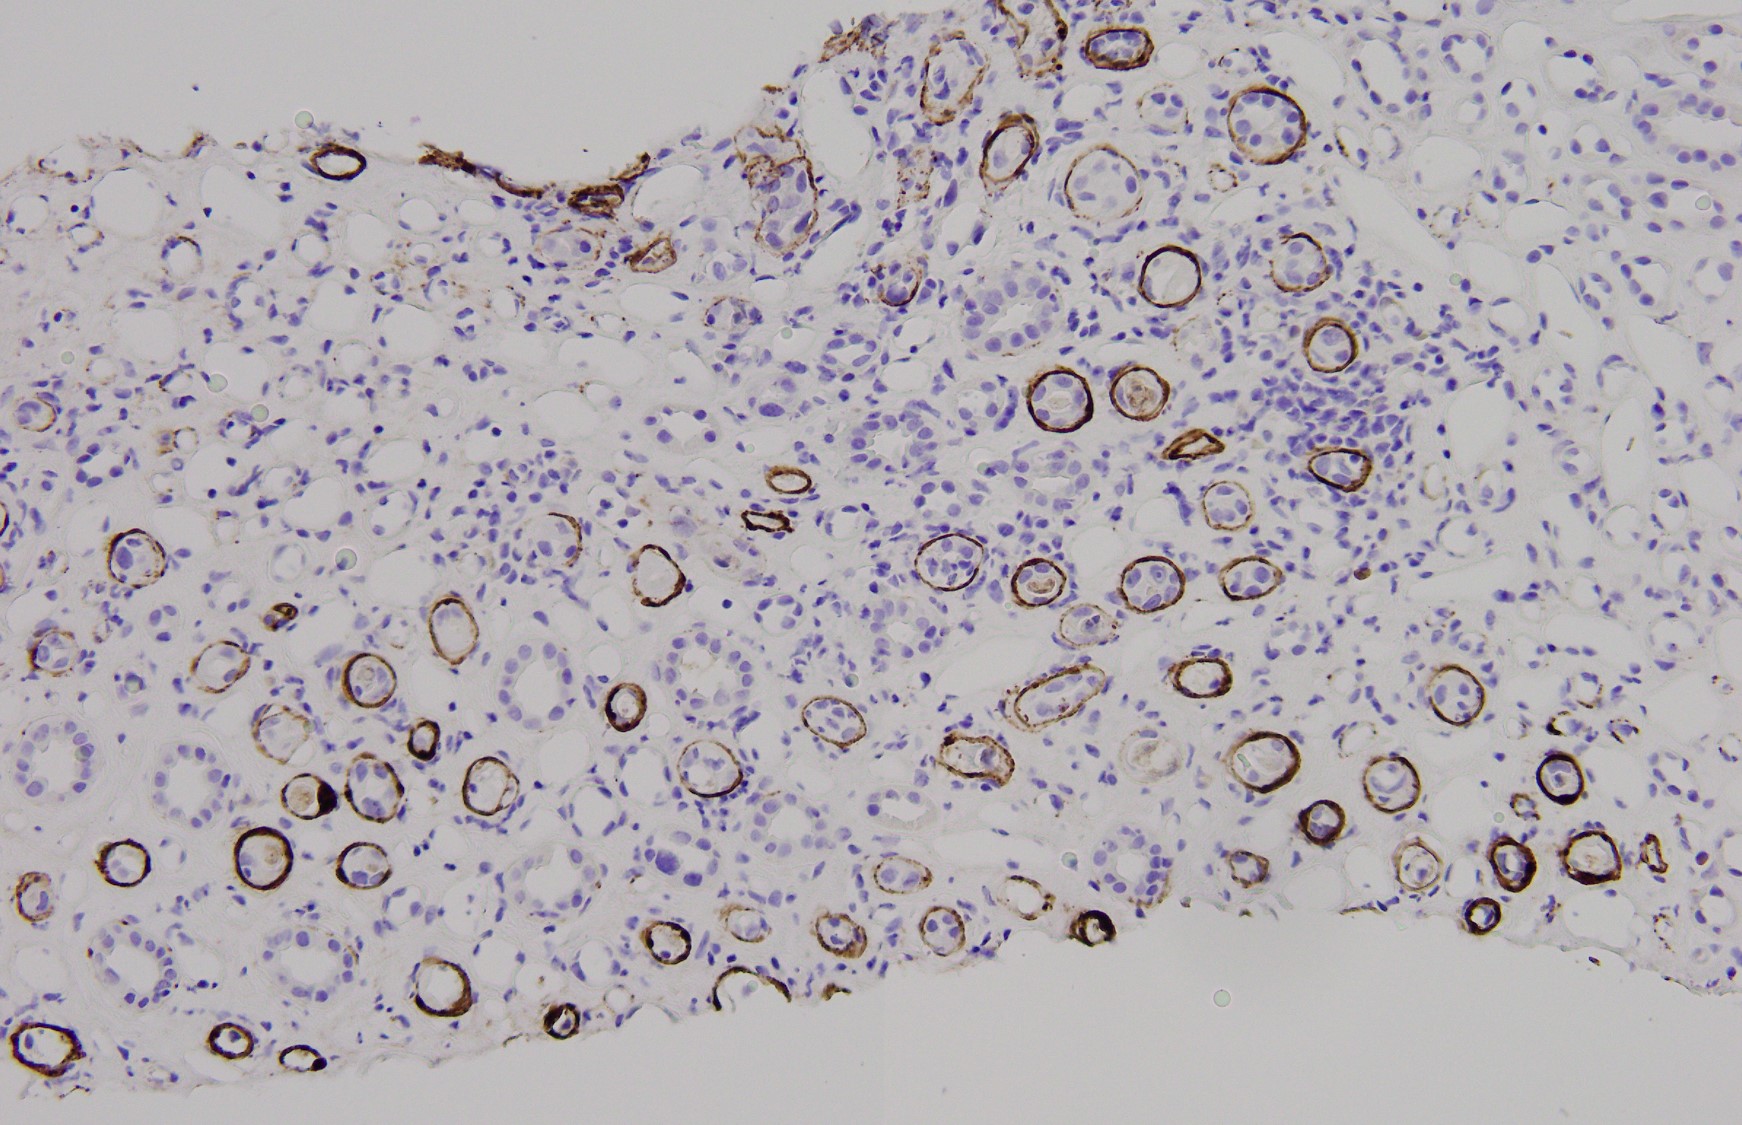

The figure 4 shows a IHC stain for C4d. Based on this picture, a concomitant antibody-mediated rejection will be diagnosed with certainty.

A. Yes

B. No

Q2: B. No

It is not always easy of straightforward to distinguish BK nephropathy from acute rejection, and very difficult to diagnose a coexisting lesion including both of them. T cell-mediated rejection shares similar histopathologic features with BK nephropathy, such as focal and brisk interstitial inflammation and tubulitis (shown in Fig. 1). However, typical viral cytopathic changes are more common in BK nephropathy, such as nuclear enlargement and intranuclear infusion (Fig. 2, yellow arrow) and features resenbling so called "decoy cells" in urine cytology (Fig. 2, red arrow). SV-40 large T antigen staining with IHC confirms a diagnosis of polyomavirus infection (shown in Fig. 3), but can't differentiate BK from JC virus. Interestingly, some patients with BK nephropathy shows C4d deposits in the tubular basement membrane (Fig. 4), but not the typical pattern of peritubular linear C4d stain for antibody-mediate rejection.